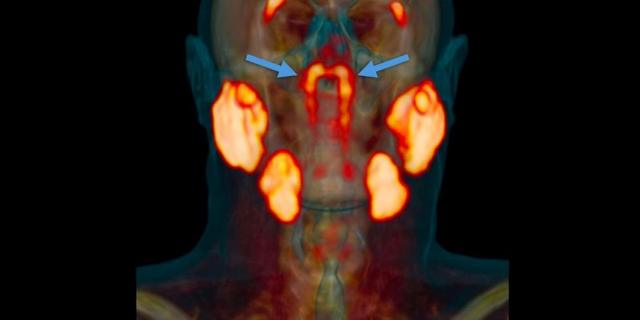

As novas glândulas ficam atrás do nariz, no encontro com a garganta

Eles identificaram o que acreditam ser novas glândulas localizadas atrás do nariz, no encontro com a garganta.

Estas setas mostram onde os pesquisadores encontraram os 'órgãos'

As possíveis novas glândulas foram encontradas no topo da garganta